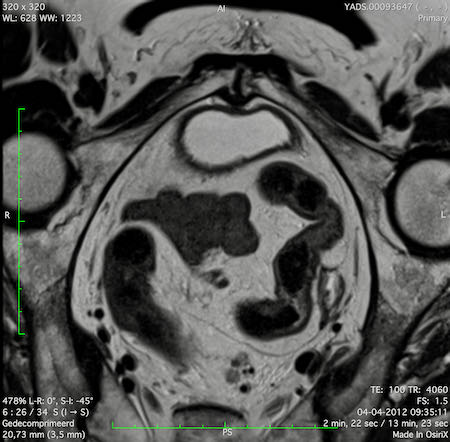

Hình ảnh

Các hình ảnh được cung cấp cho thấy ung thư biểu mô tế bào nhẫn với tình trạng dày lan tỏa thành trực tràng, hình ảnh bia bắn điển hình, và sự xâm lấn mỡ mạc treo trực tràng.